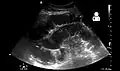

Causes of bowel obstruction include adhesions, hernias, volvulus, endometriosis, inflammatory bowel disease, appendicitis, tumors, diverticulitis, ischemic bowel, tuberculosis and intussusception.[1][2] Small bowel obstructions are most often due to adhesions and hernias while large bowel obstructions are most often due to tumors and volvulus.[1][2] The diagnosis may be made on plain X-rays; however, CT scan is more accurate.[1] Ultrasound or MRI may help in the diagnosis of children or pregnant women.[1]

Radiological signs of bowel obstruction include bowel distension (small bowel loops dilated >3 cm) and the presence of multiple (more than 2) air-fluid levels on supine and erect abdominal radiographs.[16] Ultrasounds may be as useful as CT scanning to make the diagnosis.[17]